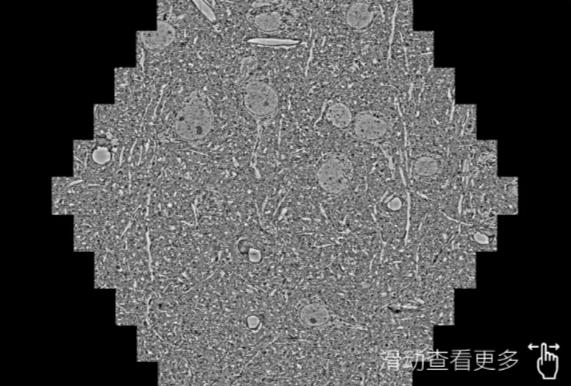

鼠脑切片。左图使用绍兴蔡司绍兴扫描电镜MultiSEM706对165μmx143pm面积区域成像,耗时仅需1.5秒。右图为鼠脑切片中30μm区域放大效果。样品由芝加哥大学B.Kasthuri提供。

使用蔡司高速绍兴扫描电镜MultiSEM对1mm²人脑皮层组织进行高分辨成像,并对其中的各种细胞结构进行三维重构分析。左图展示了2x3mm²组织平面中锥体神经元的三维重构效果。右图显示了局部体积神经元三维重构。图像由哈佛大学chtman实验室提供,渲染图由D. Berger 制作。